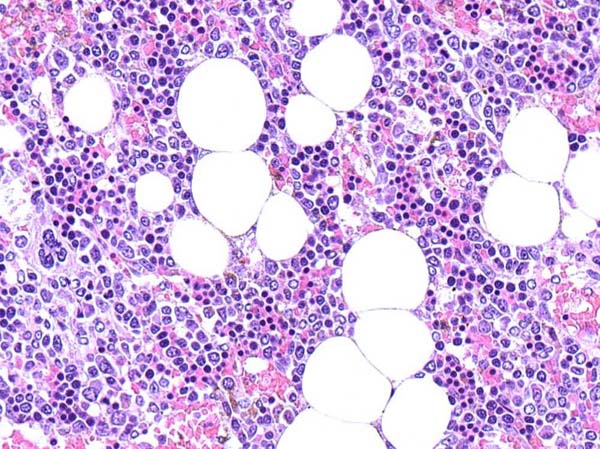

ワンちゃんが乳腺にできた複数のシコリを気にされて来院されました。bilateral mastectomyで対応しました。摘出後の病理組織検査の結果は、「R3-4間腫瘤:乳腺癌(複合型)」でそれ以外は「良性乳腺混合腫瘍」でした。無事元気に退院し、その後再発もなく経過は良好です。よかったね。